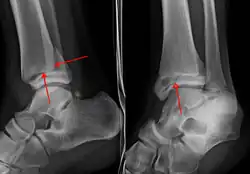

On clinical examination, it is important to evaluate the exact location of the pain, the range of motion and the condition of the nerves[11]. It is important to palpate the calf bone (fibula) because there may be an associated fracture proximally (Maisonneuve fracture)[12], and to palpate the sole of the foot to look for a Jones fracture at the base of fifth metatarsal [13]Evaluation of ankle injuries for fracture is done with the Ottawa ankle rules, a set of rules that were developed to minimize unnecessary X-rays.[14] There are three x-ray views in a complete ankle series: anteroposterior, lateral, and oblique [15]. The mortise view an anteroposterior x-ray taken with the ankle internally rotated until the lateral malleolus is on the same horizontal plane as the medial malleolus, resulting in a position where there normally is no superimposition of tibia and fibula on each other.[16]

X-ray

On X-rays, there can be a fracture of the medial malleolus, the lateral malleolus, or of the anterior/posterior margin of the distal tibia. [17] If both the lateral and medial malleoli are broken, this is called a bimalleolar fracture[18]. If the posterior malleolus is also fractured, this is called a trimalleolar fracture. [19]